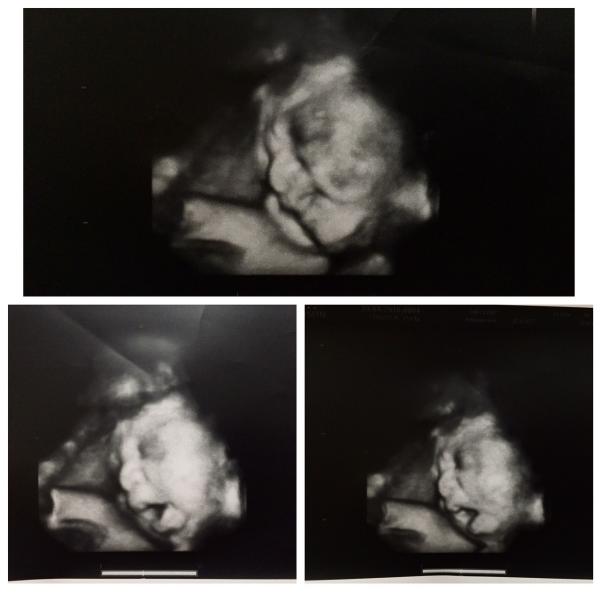

Сегодня сходили на 3 плановое узи, довоооольные🙌🏻

Увидели своего второго сыночка, все у нас отлично👌🏻 весим 2095 гр💪🏻 хотя не знаю, сколько старший был в этих сроках)

Ходили кстати к Кемельбековой, блиин так понравилось у нее, после узи муж спросил, почему раньше к ней не ходили)) жалко что это последнее узи, так бы только к ней пошла) посмеялись, распечатала нам 8 штук снимков, с разных ракурсов, так классно👍🏻

Пс: на снимках сынок улыбается и зевает, так прикольно))) нос кажись мамкин👃🏼😬